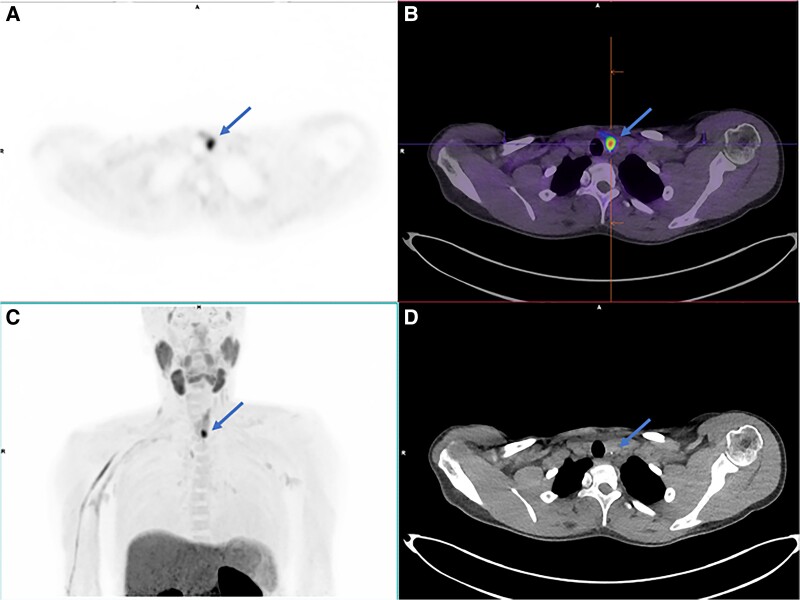

Successful Localization of Recurrent MEN-1-Associated Hyperparathyroidism With 18F-Fluorocholine PET/CT.